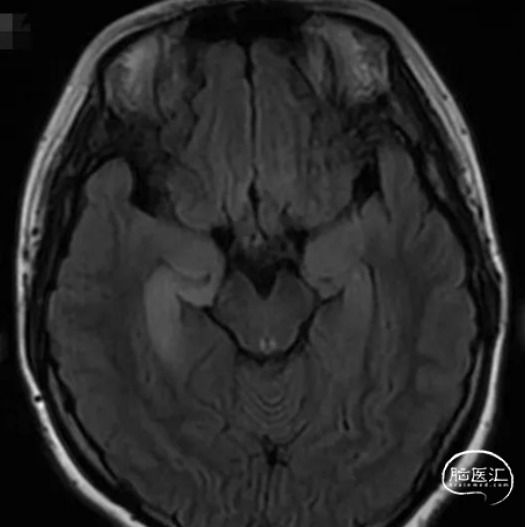

头颅MRI

1

2

3

4

头颅MR:双侧海马及杏仁核,双侧岛叶,左侧颞叶,双侧扣带回异常信号影。